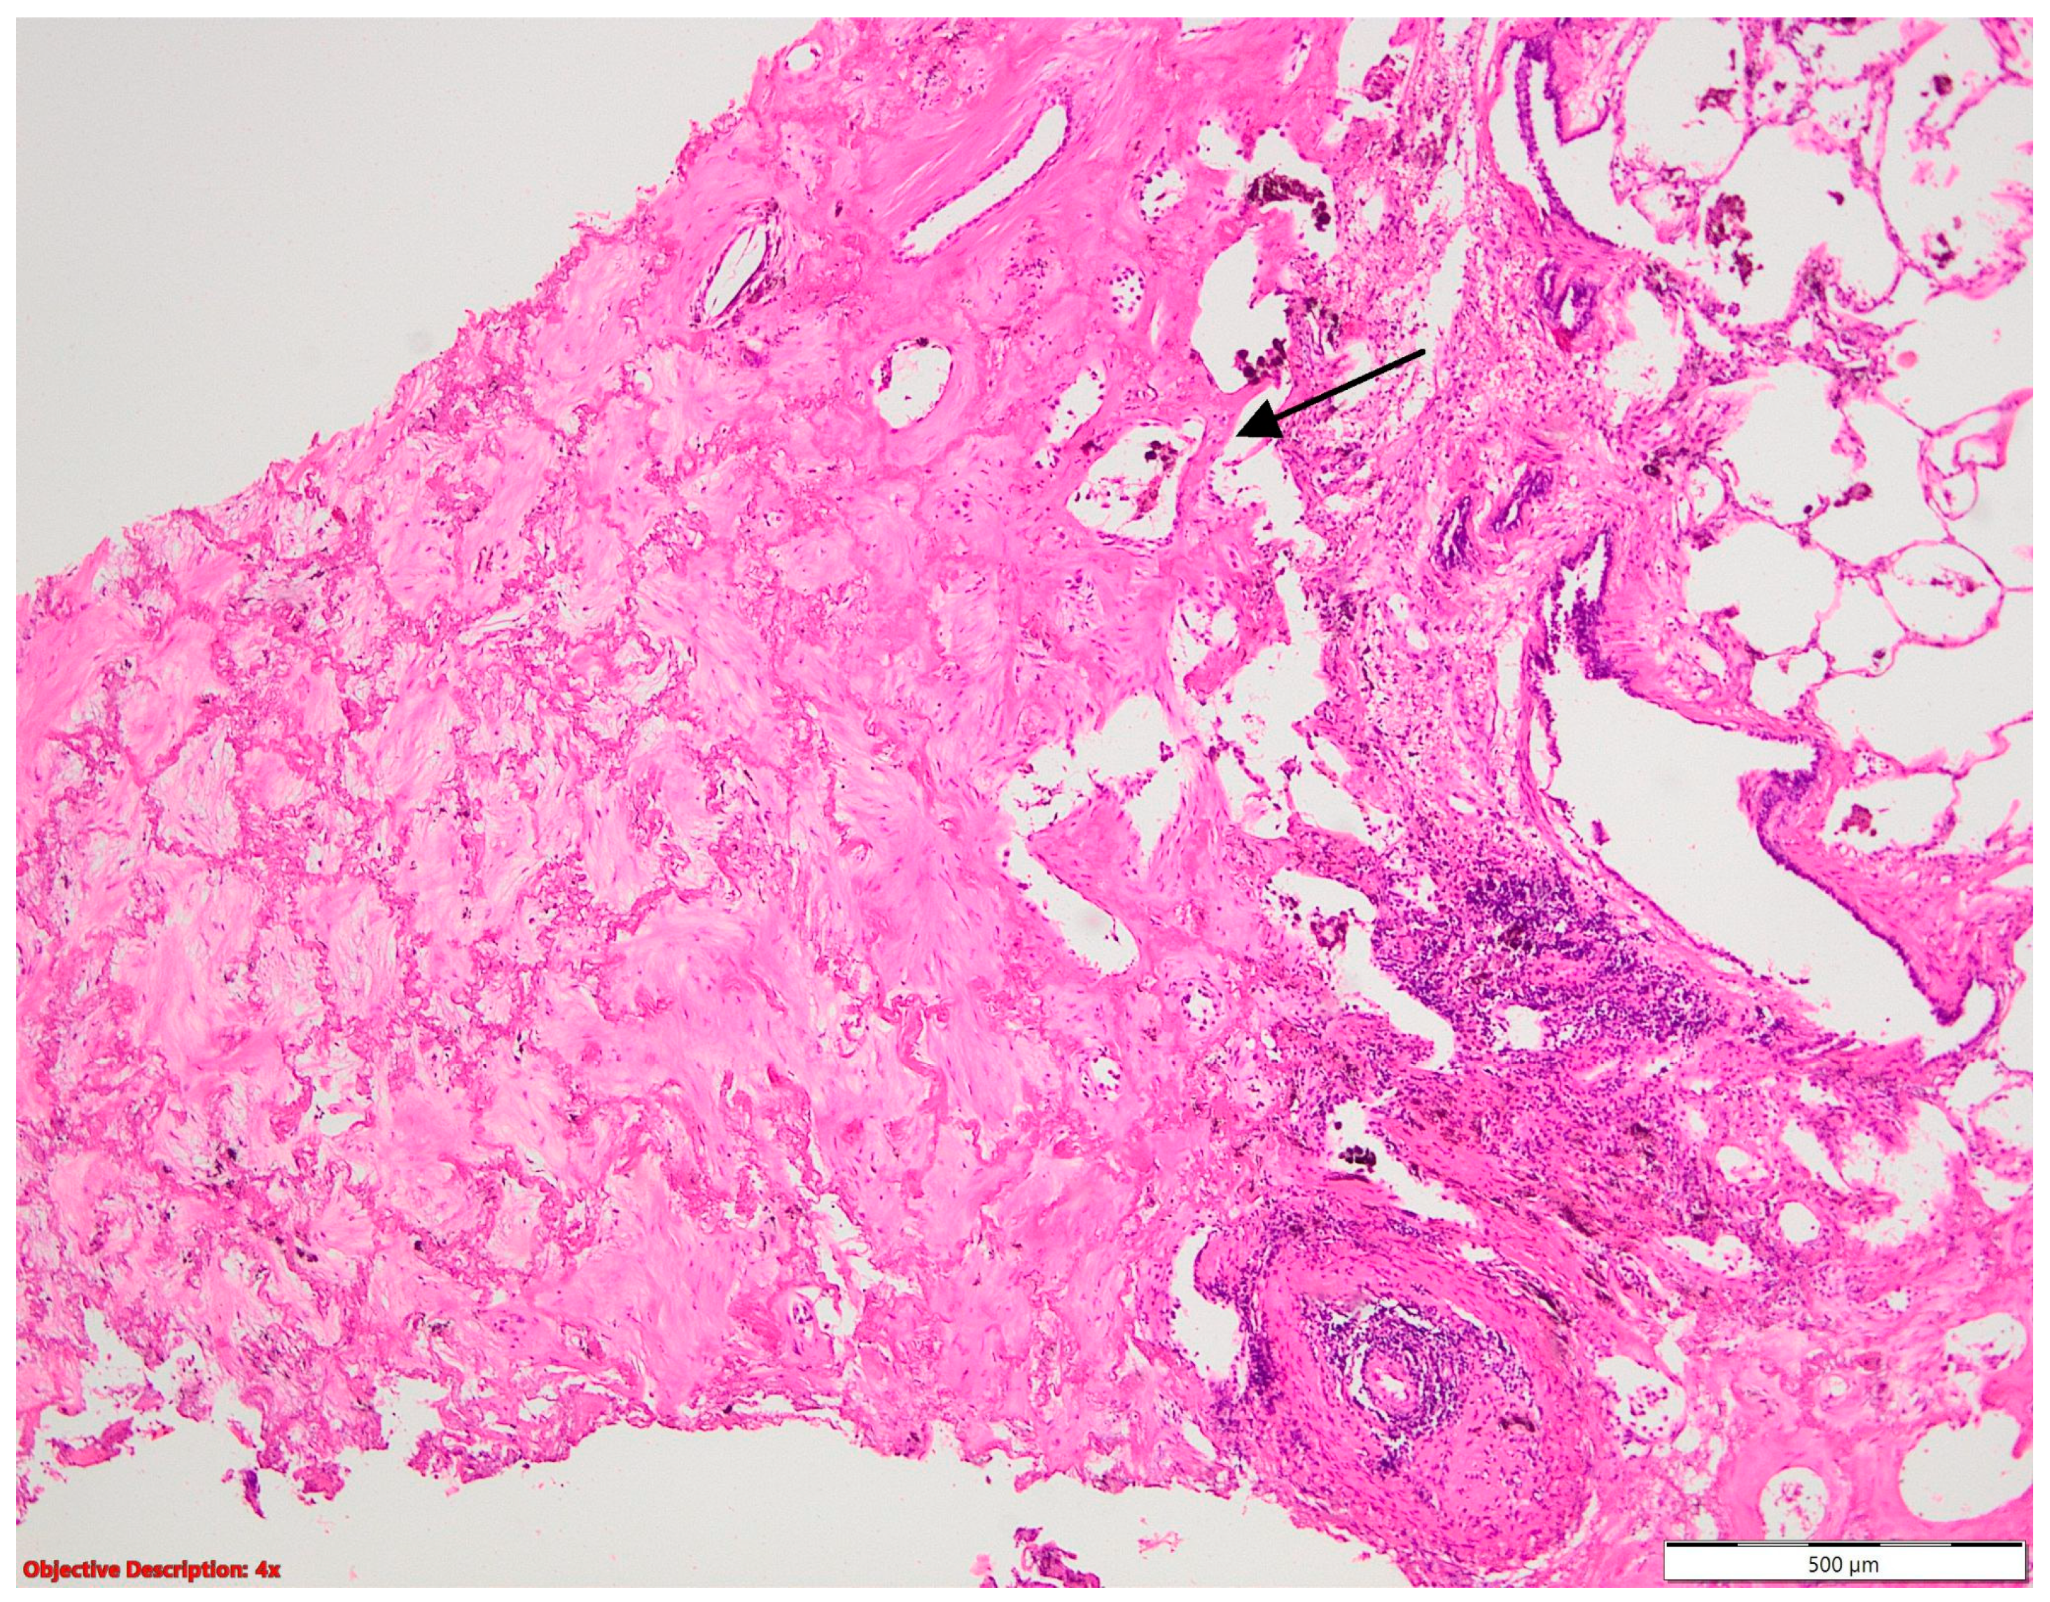

Figure 4.

Fibronodular lesion (left side) in the lung parenchyma (right side); HE, 40×.

Regarding the high prevalence of Mycobacterium tuberculosis in our country [2,7], all or part of the fibronodular lesions of the lung parenchyma (Figure 4), nodular calcification, and osseous/osteomedullary metaplasia (Figure 5) could represent sequelae of tuberculosis.

Figure 5.

Osseous metaplasia in the lung (→: lung parenchima); HE, 40×.